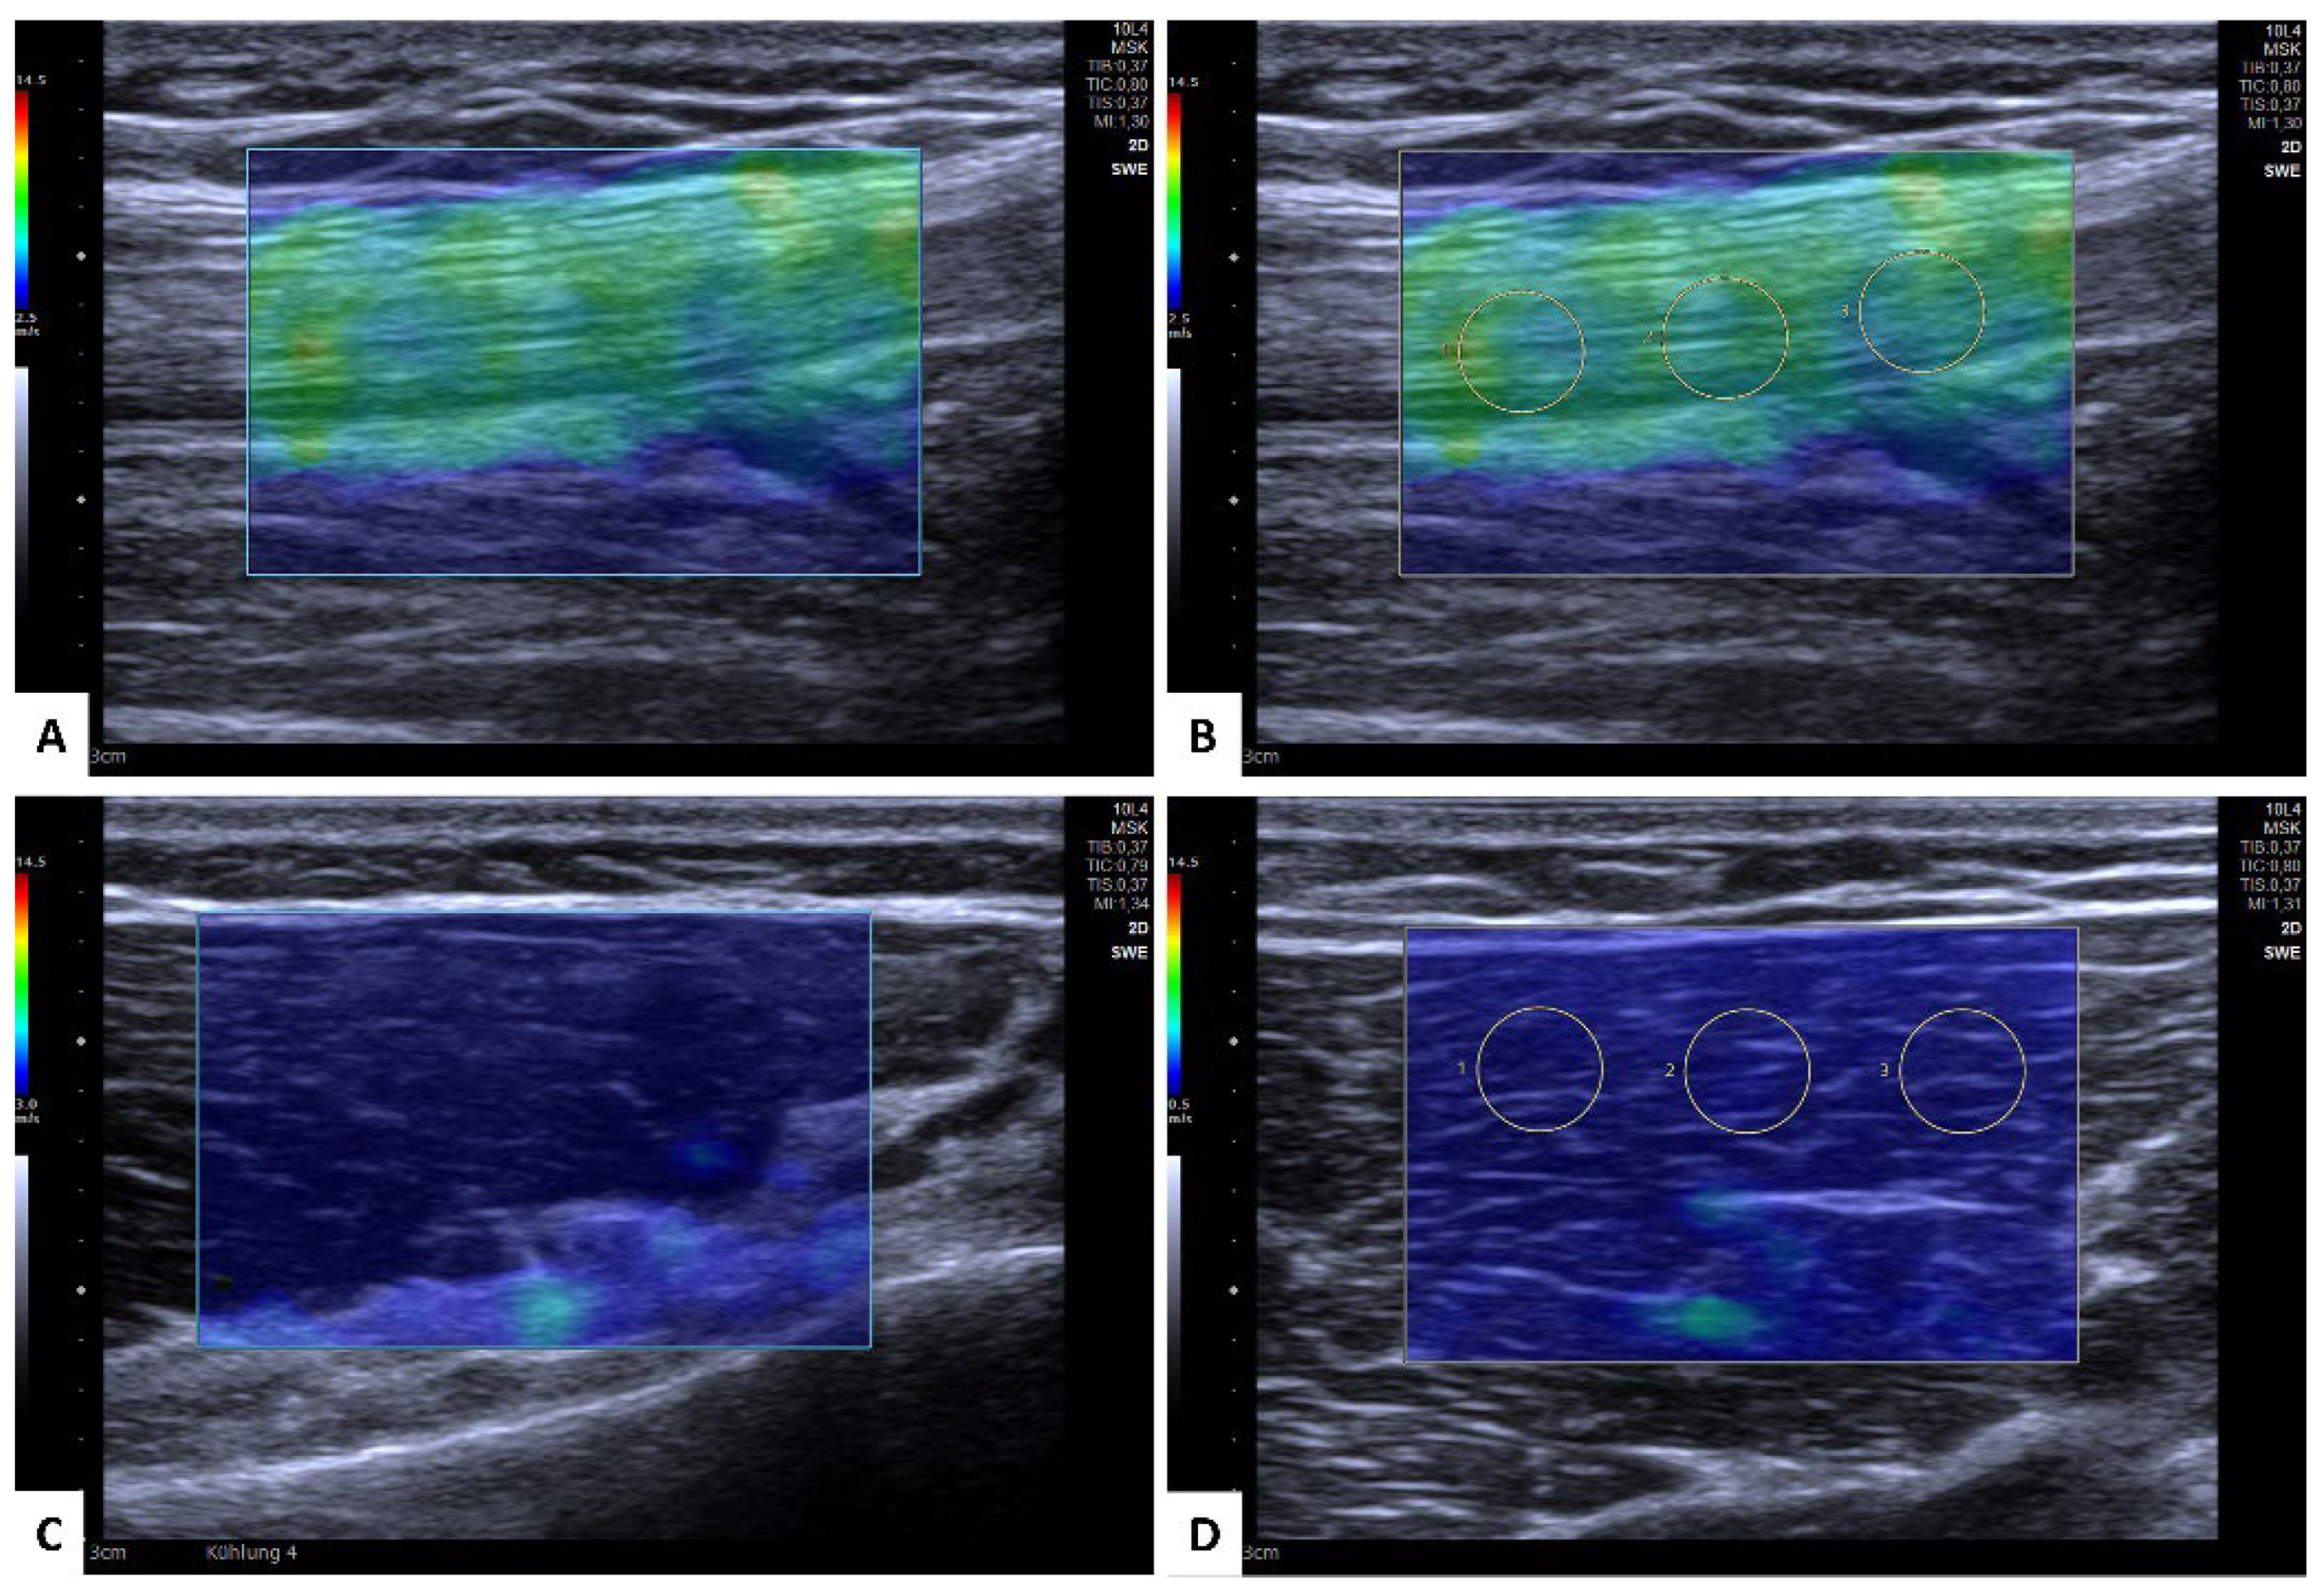

2.2. Ultrasound-Based Shear Wave Elastography